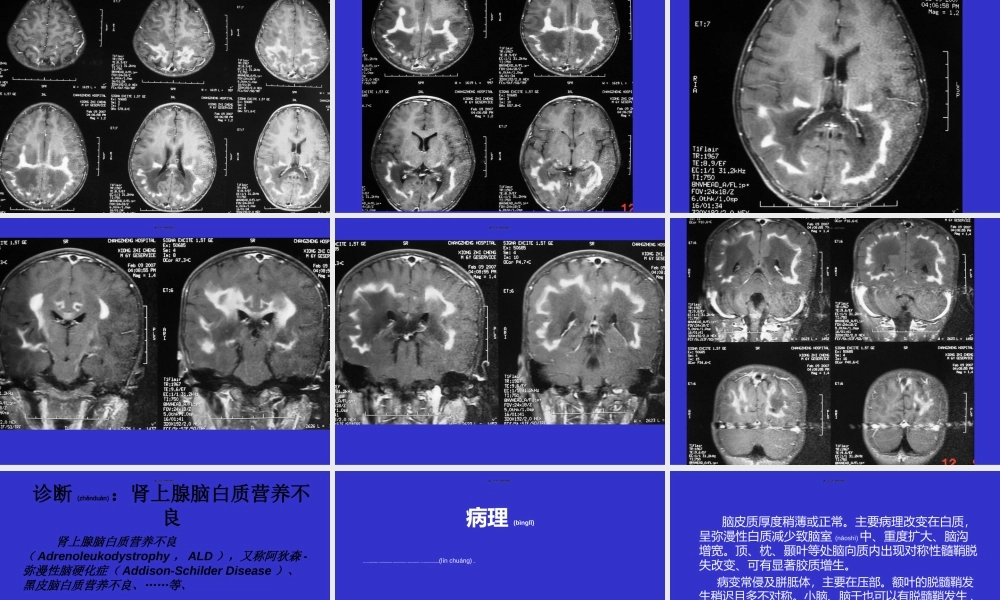

常见(chánjiàn)ɡ脑白质病梅河口市新华医院第一页,共四十四页。第一页,共四十四页。第二页,共四十四页。第二页,共四十四页。第三页,共四十四页。第三页,共四十四页。第四页,共四十四页。第四页,共四十四页。第五页,共四十四页。第五页,共四十四页。第六页,共四十四页。第六页,共四十四页。第七页,共四十四页。第七页,共四十四页。第八页,共四十四页。第八页,共四十四页。第九页,共四十四页。第九页,共四十四页。第十页,共四十四页。第十页,共四十四页。第十一页,共四十四页。第十一页,共四十四页。第十二页,共四十四页。第十二页,共四十四页。第十三页,共四十四页。第十三页,共四十四页。第十四页,共四十四页。第十四页,共四十四页。第十五页,共四十四页。第十五页,共四十四页。第十六页,共四十四页。第十六页,共四十四页。第十七页,共四十四页。第十七页,共四十四页。第十八页,共四十四页。第十八页,共四十四页。第十九页,共四十四页。第十九页,共四十四页。诊断(zhěnduàn):肾上腺脑白质营养不良肾上腺脑白质营养不良(Adrenoleukodystrophy,ALD),又称阿狄森-弥漫性脑硬化症(Addison-SchilderDisease)、黑皮脑白质营养不良、……等、1912年Schilder首次报道,Blaw于1964年正式命名为肾上腺脑白质营养不良。该病是脑白质营养不良中最常见的一种,通常是指一组X染色体连锁(liánsuǒ)隐性遗传的疾病(简称X-ALD),但广义上也包括一组常染色体隐性遗传的ALD(简称为A-ALD,automosalALD),即指新生儿ALD。第二十页,共四十四页。第二十页,共四十四页。病理(bìnglǐ)•目前一般认为由于溶酶体过氧化酶的缺乏,导致极长链脂肪酸在细胞异常堆积,特别在脑白质和肾上腺皮质内的沉积、导致脑白质和肾上腺皮质的破坏,从而产生特征性的脑白质和肾上腺皮质损害的临床(línchuánɡ)症状。第二十一页,共四十四页。第二十一页,共四十四页。脑皮质厚度稍薄或正常。主要病理改变在白质,呈弥漫性白质减少致脑室(nǎoshì)中、重度扩大、脑沟增宽。顶、枕、颞叶等处脑向质内出现对称性髓鞘脱失改变、可有显著胶质增生。病变常侵及胼胝体,主要在压部。额叶的脱髓鞘发生稍迟且多不对称。小脑、脑干也可以有脱髓鞘发生,内囊、外囊、锥体束等可见连续性髓鞘脱失改变。並可出现鈣质沆积,有时很广泛而显著。第二十二页,共四十四页。第二十二页,共四十四页。这些髓鞘脱失区从外向内可分为三个病理(bìnglǐ)...